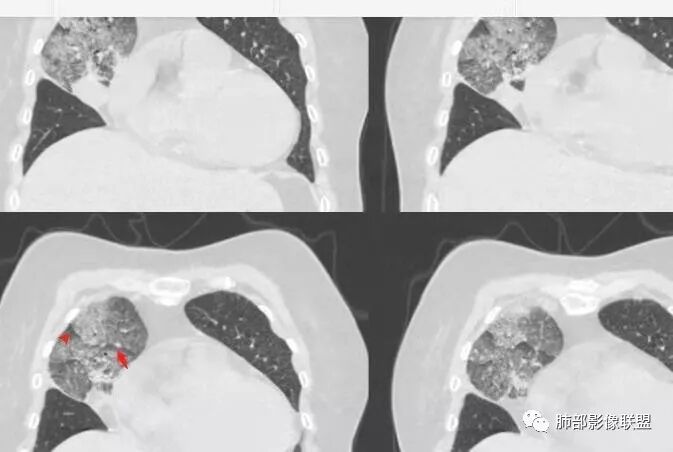

胸CT:右肺上叶实变内可见支气管充气征,近端支气管狭窄,远端扩张,周围可见毛玻璃影,右肺中叶支气管闭塞,并可见气道壁钙化,右肺中叶体积缩小,实变内可见空洞,并可见气液平面,空洞周围可见毛玻璃样影,右肺下叶支气管开口狭窄,右肺门淋巴结肿大。纵隔窗可见病灶与壁层胸膜间隙增宽,考虑良性病变-----感染性病变------TB?

右肺上叶病变,内见钙化及空洞,支气管可见,考虑结核伴出血。

老年女性,慢性病程,咳嗽伴白色粘液痰,无发热腹痛,糖尿病,白细胞及C反应蛋白不高,血沉快,铁蛋白高。胸部CT,右肺上叶大片状实变伴磨玻璃密度影,边界不清,边缘局部膨隆,叶裂弧形下坠,实变影宽基底与胸膜相贴;右肺下叶前基底段见类似病灶;右肺中叶不张并空洞形成,空洞内见气液平面;综合考虑右肺上叶及下叶肺炎型肺癌,右肺中叶结核。

老年女性,病史1月,右肺上中叶大片状影,跨叶,上叶为主,磨玻璃为主,边界模糊,部分实变,内见空洞影和液气平面,壁光滑,支气管开口狭窄,局部有扩张,右肺门淋巴结钙化,首先考虑感染性病变,结核可能,鉴别粘液腺癌。

老年女性,亚急性起病,右肺上中叶大片状影,跨叶,上叶为主,磨玻璃为主,边界模糊,部分实变,内见空洞影和液气平面,壁光滑,洞内可见结节形成,局部有扩张,首先考虑感染性病变,结核可能;洞内可见结节样病灶,鉴别合并曲霉、肿瘤。

实变区像支气管爬行征?空洞区也有钙化和边界清楚模玻璃影

以前老师们也讲过边界清楚的模玻璃影及反晕征注意TB

3.熊老师告诉我们:肺结核可以有磨玻璃,这个我以前一直不知道,右肺门淋巴结有钙化,病灶内纵膈窗隐约细细点状钙化,所以结核磨玻璃可以,

这个病人可以当做干酪性肺炎的扩大延长版